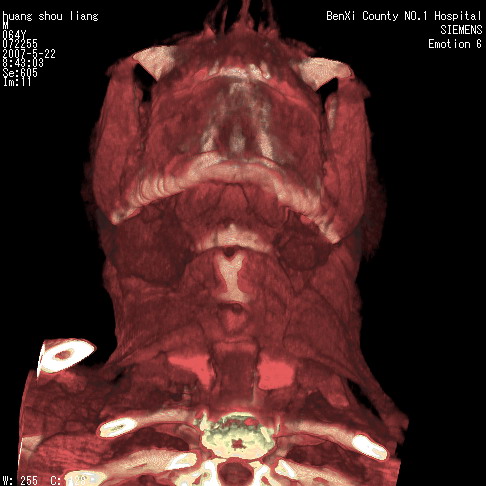

男性,64岁。颈部包块8年。最近增大。

对不起大家,可能是片子发太多有点乱,正常腮腺在下颌角的外侧,颌下腺在下颌体的中部内侧,本例在下颌角内侧偏下,和腺体一点关系都没有,从vrt和mpr上可以很明显看出来,再者肿块是好多粘连在一块的,大家在仔细看看,左侧可能也是吧,我还是考虑为肿大的淋巴结融合在一块,但性质??????

右侧腮腺下部均匀软组织密度肿块,外形不规则,与周围组织分界清晰,考虑右侧腮腺混合瘤或多形性腺瘤。

大家好,病理结果出来了,如大家所说,颌下腺混合瘤。

画个图共同讨论一下解剖关系。